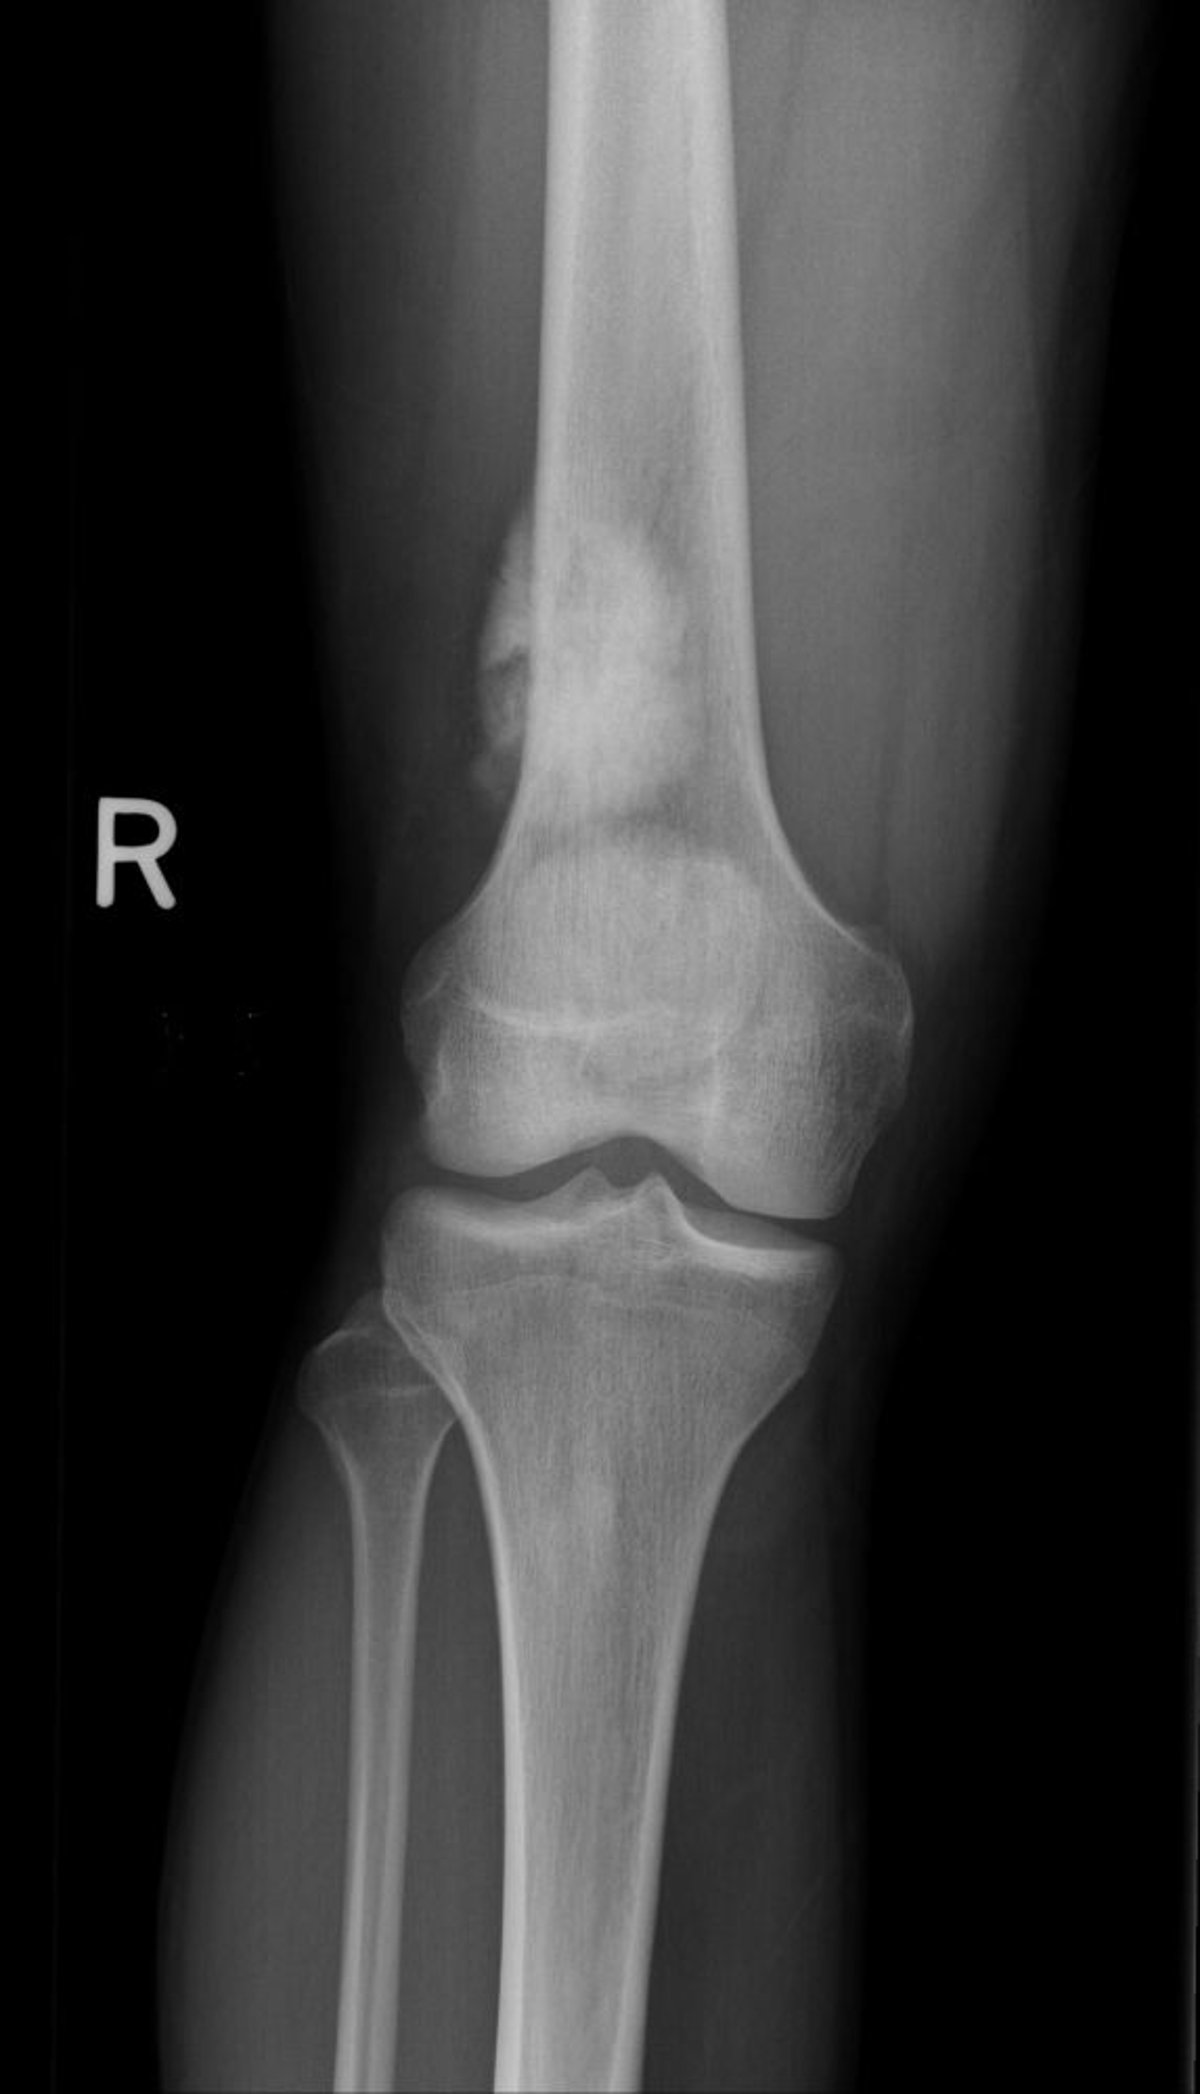

تُظهر هذه الصورة الشعاعية للركبة وجود ساركومة عظمية في عظم الفخذ فوق مستوى الركبة.

جرى استخدام الصورة بعد موافقة أصحابها Michael J.Joyce, MD, and Hakan Ilaslan, MD.